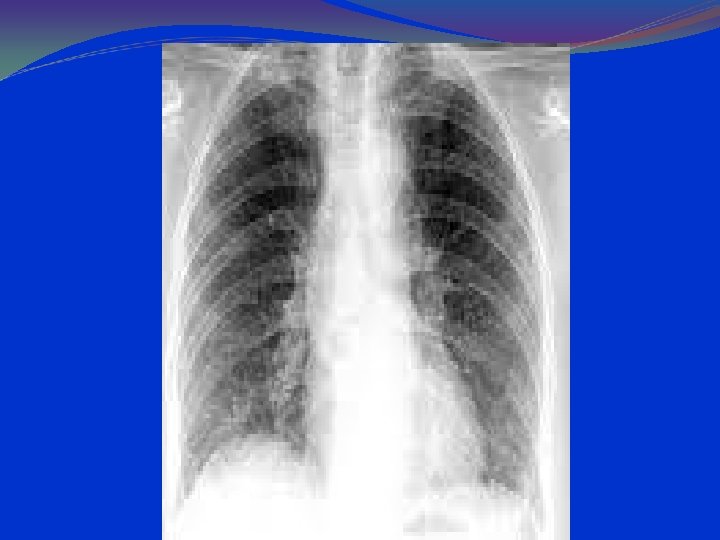

LABORATORY AND IMAGISTICS Complete blood count (CBC) with white blood cell (WBC) count within normal limits. 2/3 of the children have WBC counts of 10, 000 to 15, 000/μL. Most have 50 to 75% lymphocytes Serum chemistries may be affected in dehydration. Arterial blood gases (ABG) in severely ill patients, with mechanical ventilation. Chest radiographs should include anterior-posterior (AP) and lateral views. Hyperinflation and patchy infiltrates ; these findings are nonspecific and may be observed in asthma, viral or atypical pneumonia, and aspiration. Focal atelectasis Air trapping Flattened diaphragm Increased anteroposterior diameter

lung hyperinflation with a flattened diaphragm and bilateral atelectasis in the right apical and left basal regions